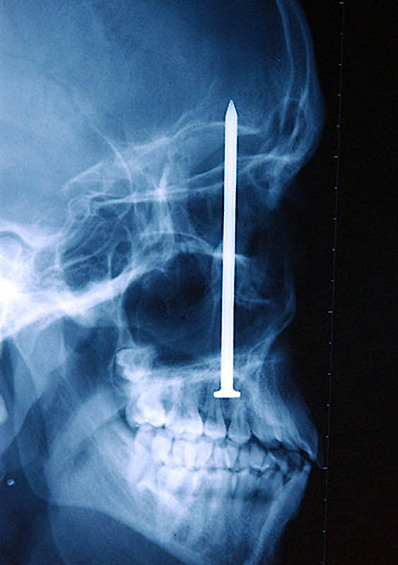

12 рентген‑фотографий, которые доказывают: идиотизм неистребим

Зачем и почему люди глотают разные странные вещи? Никто не знает точно, но медики утверждают, что таких “умников” гораздо больше, чем мы думаем.

Рентгенологи — люди с особо развитым чувством юмора. То, что они порой видят на снимках, у нормального человека вызовет настоящую истерику — а они только хмыкнут и отправят к хирургу. Что поделать, не расстраиваться же из-за каждого курьеза.